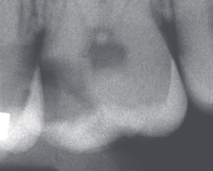

X 光显示龋坏接近牙髓腔

图片来自Bjørndal L, Simon S, Tomson PL, Duncan HF. Management of deep caries and the exposed pulp. International Endodontic Journal. 2019.